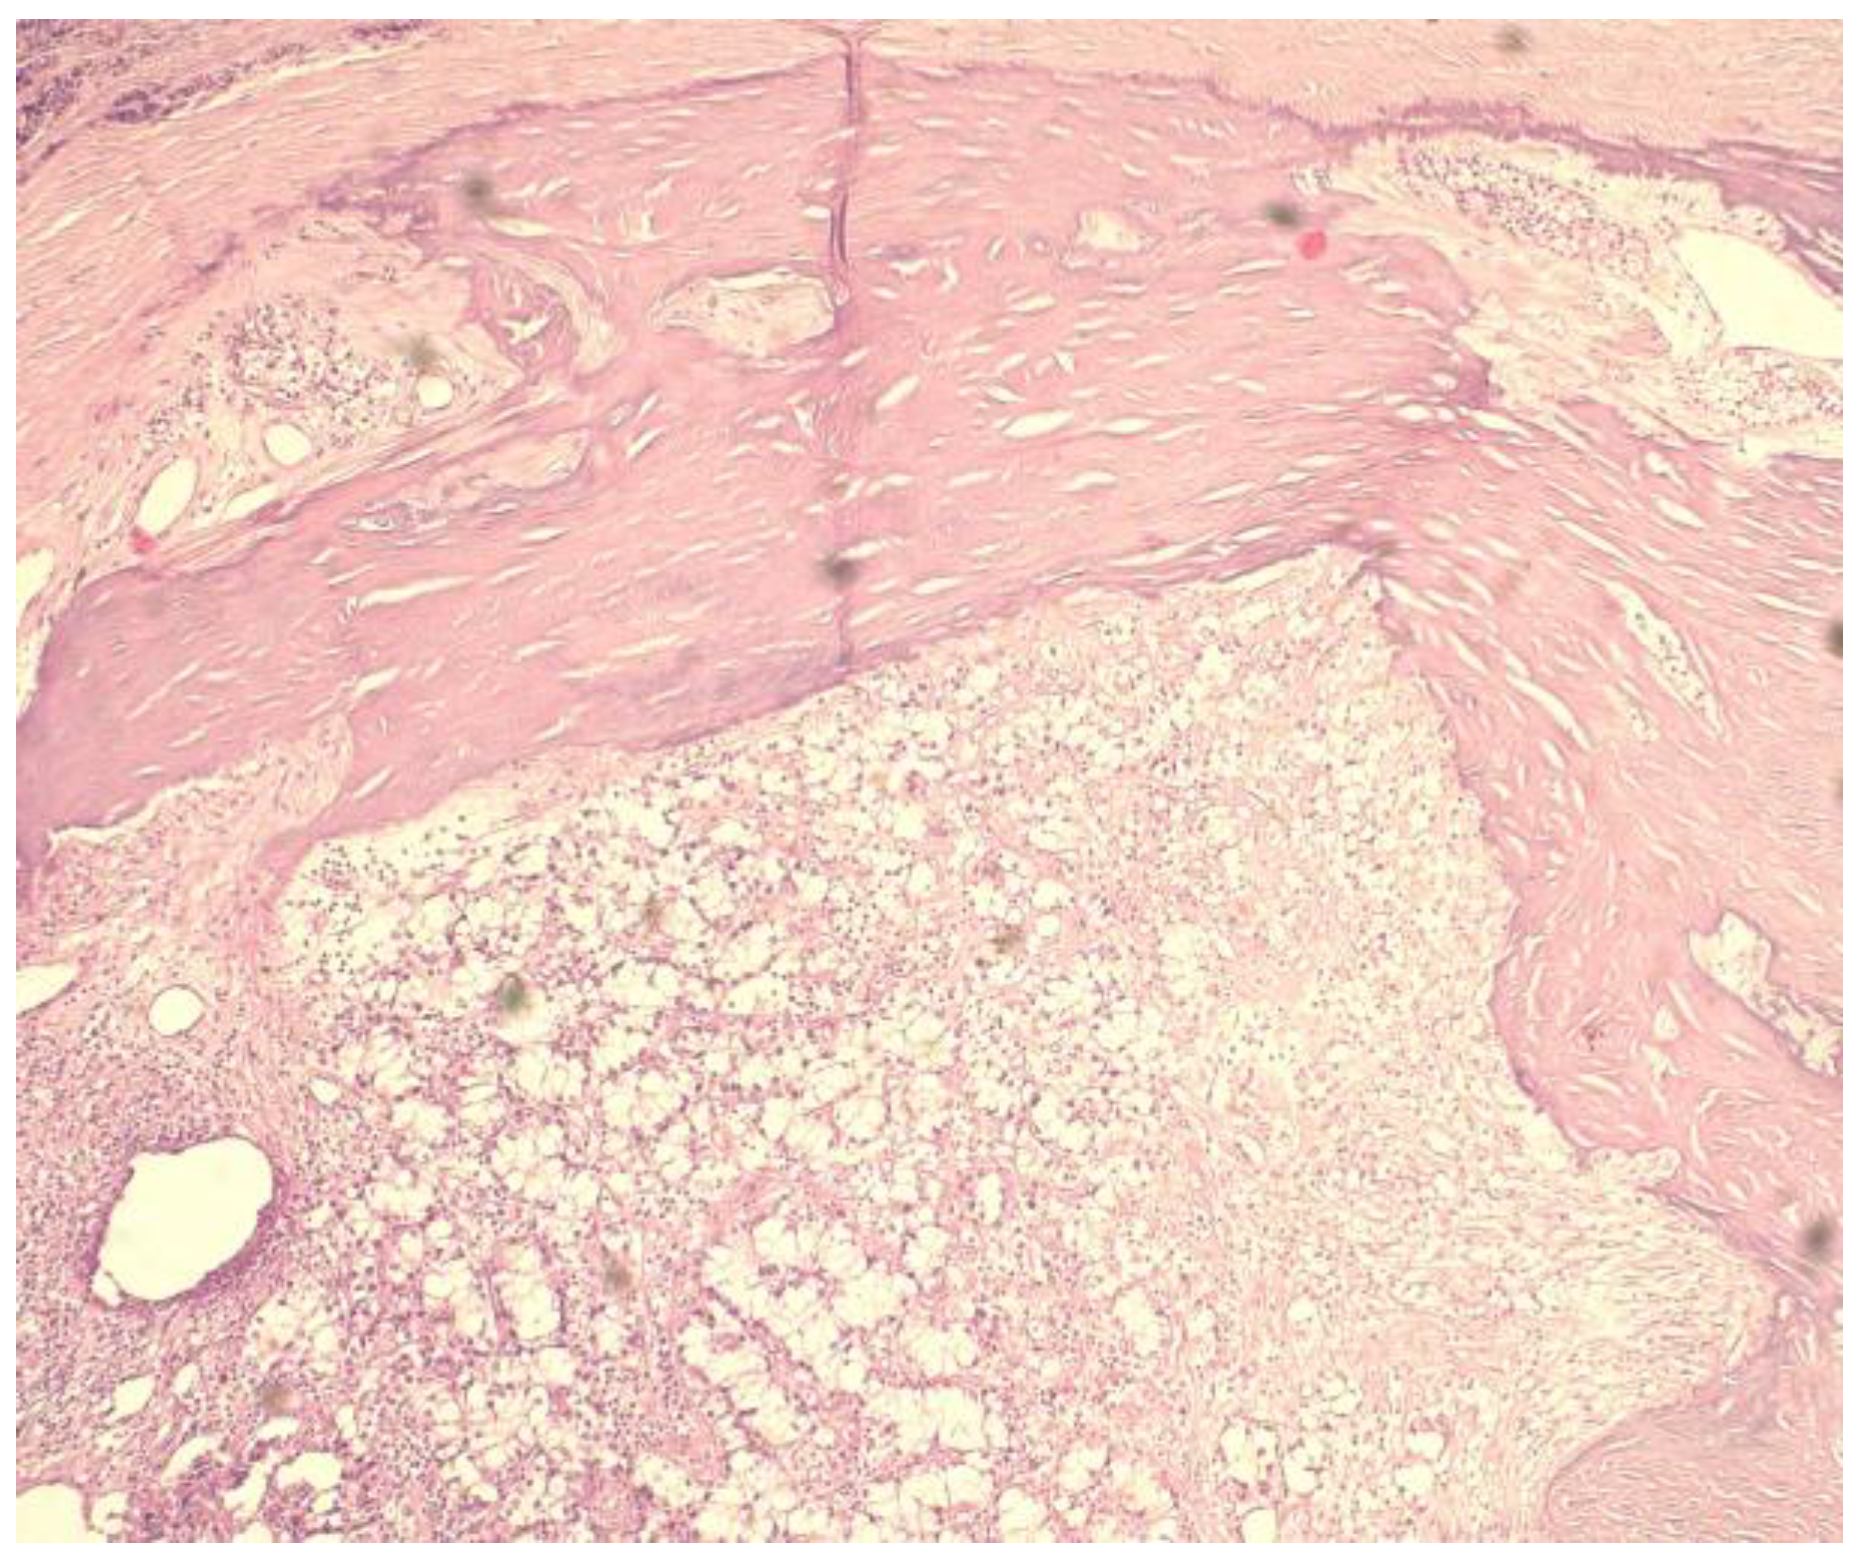

4. Diagnosis